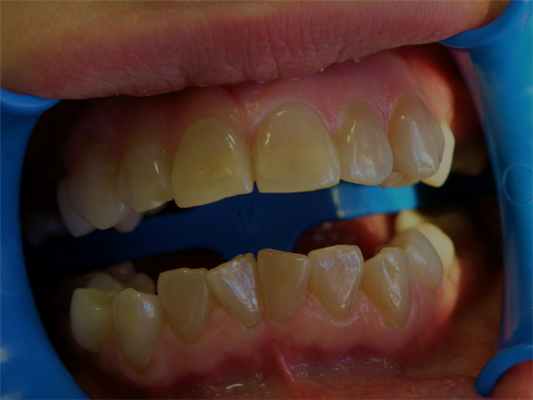

Поражение зубов ограничивается дефектом эмали. На рентгенограмме конфигурация пульпарной камеры и корневых каналов выглядит нормальной. Различия во внешнем виде и структуре эмали зависят от периода развития, на котором находилась эмаль в период формирования дефекта. При гипопластическом типе аномалии эмалевая матрица не полностью сформирована, а т. к. постепенно происходит минерализация эмалевой матрицы, эмаль становится твердой, но ее количество уменьшено и она имеет грубую пятнистую поверхность (рис. 7.27).

Рис. 7.29. А - несовершенный амелогенез. Постоянные зубы покрыты тонким слоем пигментированной эмали; Б - на рентгенограмме существенных изменений в морфологии корней зубов не наблюдается. Коронки покрыты тонким слоем эмали.

При другом типе несовершенного амелогенеза эмаль тонкая, гладкая, имеет коричневато-желтый цвет. Такая эмаль мало подвержена истиранию и кариесу (рис. 7.29 и 7.30).